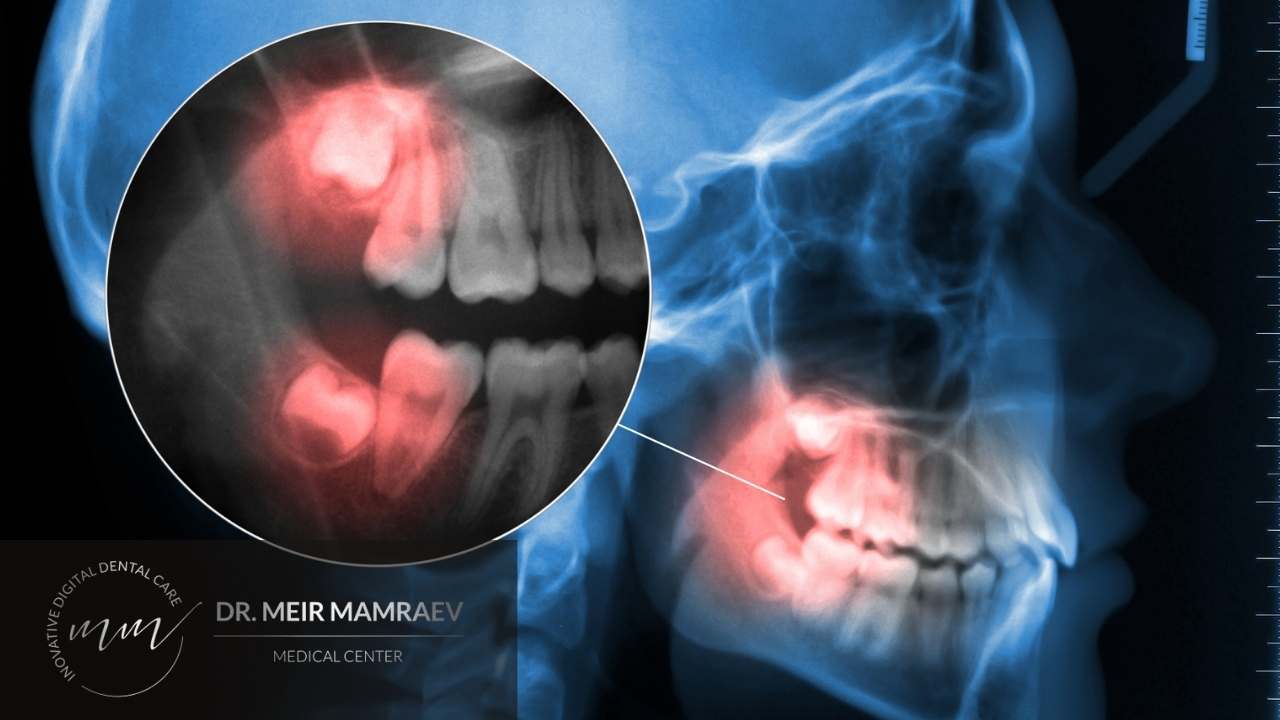

שן בינה כלואה זו שן שלא מצליחה לבקוע כראוי, כפי שצריך לקרות באופן טבעי כאשר מתבגרים. כלומר שיני בינה כלואות לא בולטות מחוץ לחניכיים בדומה לשיניים אחרות שנראות לעין בתוך קשת השיניים. מצב זה נוצר כאשר אין די מקום פנוי בלסת לאחר שיתר השיניים צמחו קודם לכן, בגילאים הצעירים.

לעיתים השן לא תהיה כלואה לגמרי אלא בחלקה או שהיא תצמח אבל בצורה עקומה (במידה רבה או מעטה). כמו כן לעיתים שן הבינה הכלואה תישאר שקועה מתחת לחניכיים או שהיא תהיה לחלוטין כלואה בתוך עצם הלסת עצמה.

אצל חלק מהמטופלים השן צומחת בצורה לא תקינה, בזווית כזאת או אחרת וכשהיא נוטה ונשענת על שן סמוכה או נוטה באלכסון כלפי חוץ או לעבר מעמקי הפה, כלפי פנים.

לא תמיד נחוש בשן הכלואה אך גם אם לא מרגישים שן בינה כלואה עם כאבים, עדיין לא מדובר במצב בריא בהכרח. אצל חלק מהמטופלים במרפאתנו נגלה את קיומה של השן הכלואה במקרה, בצילום רנטגן בביקורת שגרתית או צילום שנעשה מסיבה אחרת כגון בדיקת עששת או הרכבת כתר.